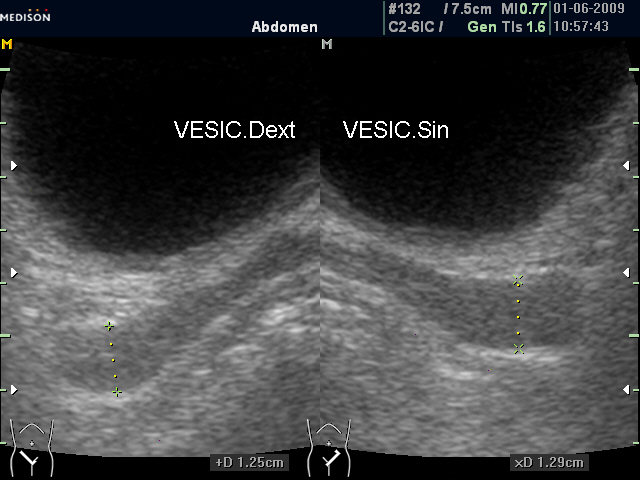

Нормальные семенные пузырьки при ТА и ТР УЗИ (фото 1 и 2).

Нормальные СП (ТА УЗИ)